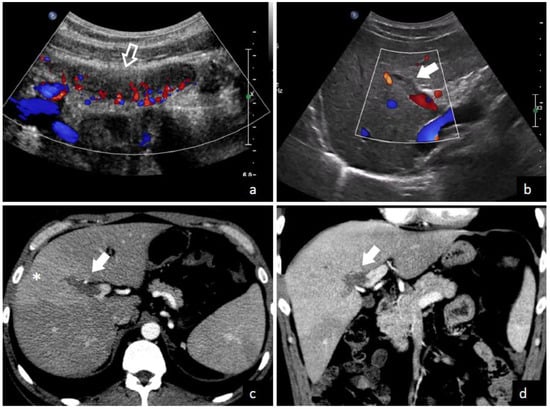

The demonstration of thrombus in the portal vein is the central finding leading to a pylephlebitis diagnosis. Both computed tomography (CT) scanning and abdominal ultrasonography can detect the presence of thrombi in the portal vein as shown in Figure 3 and Figure 4. Ultrasonography can detect the presence of echogenic material in the portal vein lumen, which can be confirmed by flow alterations on Doppler analyses [2,213]. CT scan should be preferred because of its higher definition and the additional investigative ability to identify possible abdominal or pelvic infective foci [2,39,65]. According to a recent systematic review, which enrolled studies between 2010 and 2021, the diagnosis was determined with a CT scan in 89.3% of patients and an ultrasound examination in 38.8% of patients [208]. In contrast, a previous review which included studies before 2010, found that CT scan was used only in 51% of patients. Magnetic resonance imaging (MRI) [44,210], angiography [69,91,217], endoscopic ultrasound [81], or positron emission tomography (PET) [5,42] can also be used to demonstrate portal vein thrombosis; however, their application remains limited to selected cases.

Figure 3.

A 35-year-old male with fever and severe abdominal pain was admitted to the emergency department of Trieste University Hospital. Ultrasound with color flow Doppler images (a,b) shows acute inflammation of the appendix (empty arrow in (a)) and echogenic material inside an intrahepatic branch of the portal vein without color flow signal (solid arrow), due to thrombosis. Contrast-enhanced CT images in axial (c) and coronal (d) plains confirm a filling defect in a right intrahepatic portal vein branch (solid arrows), with transient hepatic attenuation differences—THAD—(* in c) due to hepatic arterial compensatory flow in the corresponding segment.